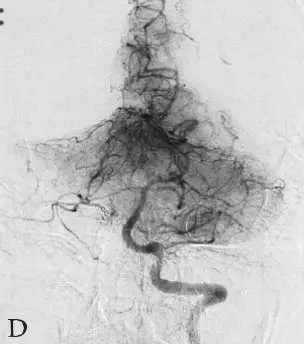

DSA:急诊全脑血管造影提示右侧颈内动脉发出变异的原始三叉动脉,该三叉动脉直接向右侧小脑前下动脉(AICA)供血区域供血,在原始三叉动脉自颈内动脉发出部位可见1枚梭形动脉瘤(图18-1B、C),右侧椎动脉发育较差,仅供血小脑后下动脉(PICA)区域(图18-1D)。右侧小脑前下动脉(AICA)未见显影,可见基底动脉发出的部分回旋支显影(图18-1E)。其余血管造影未见明显异常。

B:右侧颈内动脉造影;

C:右侧颈内动脉造影三维重建;

D:右侧椎动脉造影;

E:左侧椎动脉造影。

图18-1变异原始三叉动脉动脉瘤患者术前CT及DSA影像